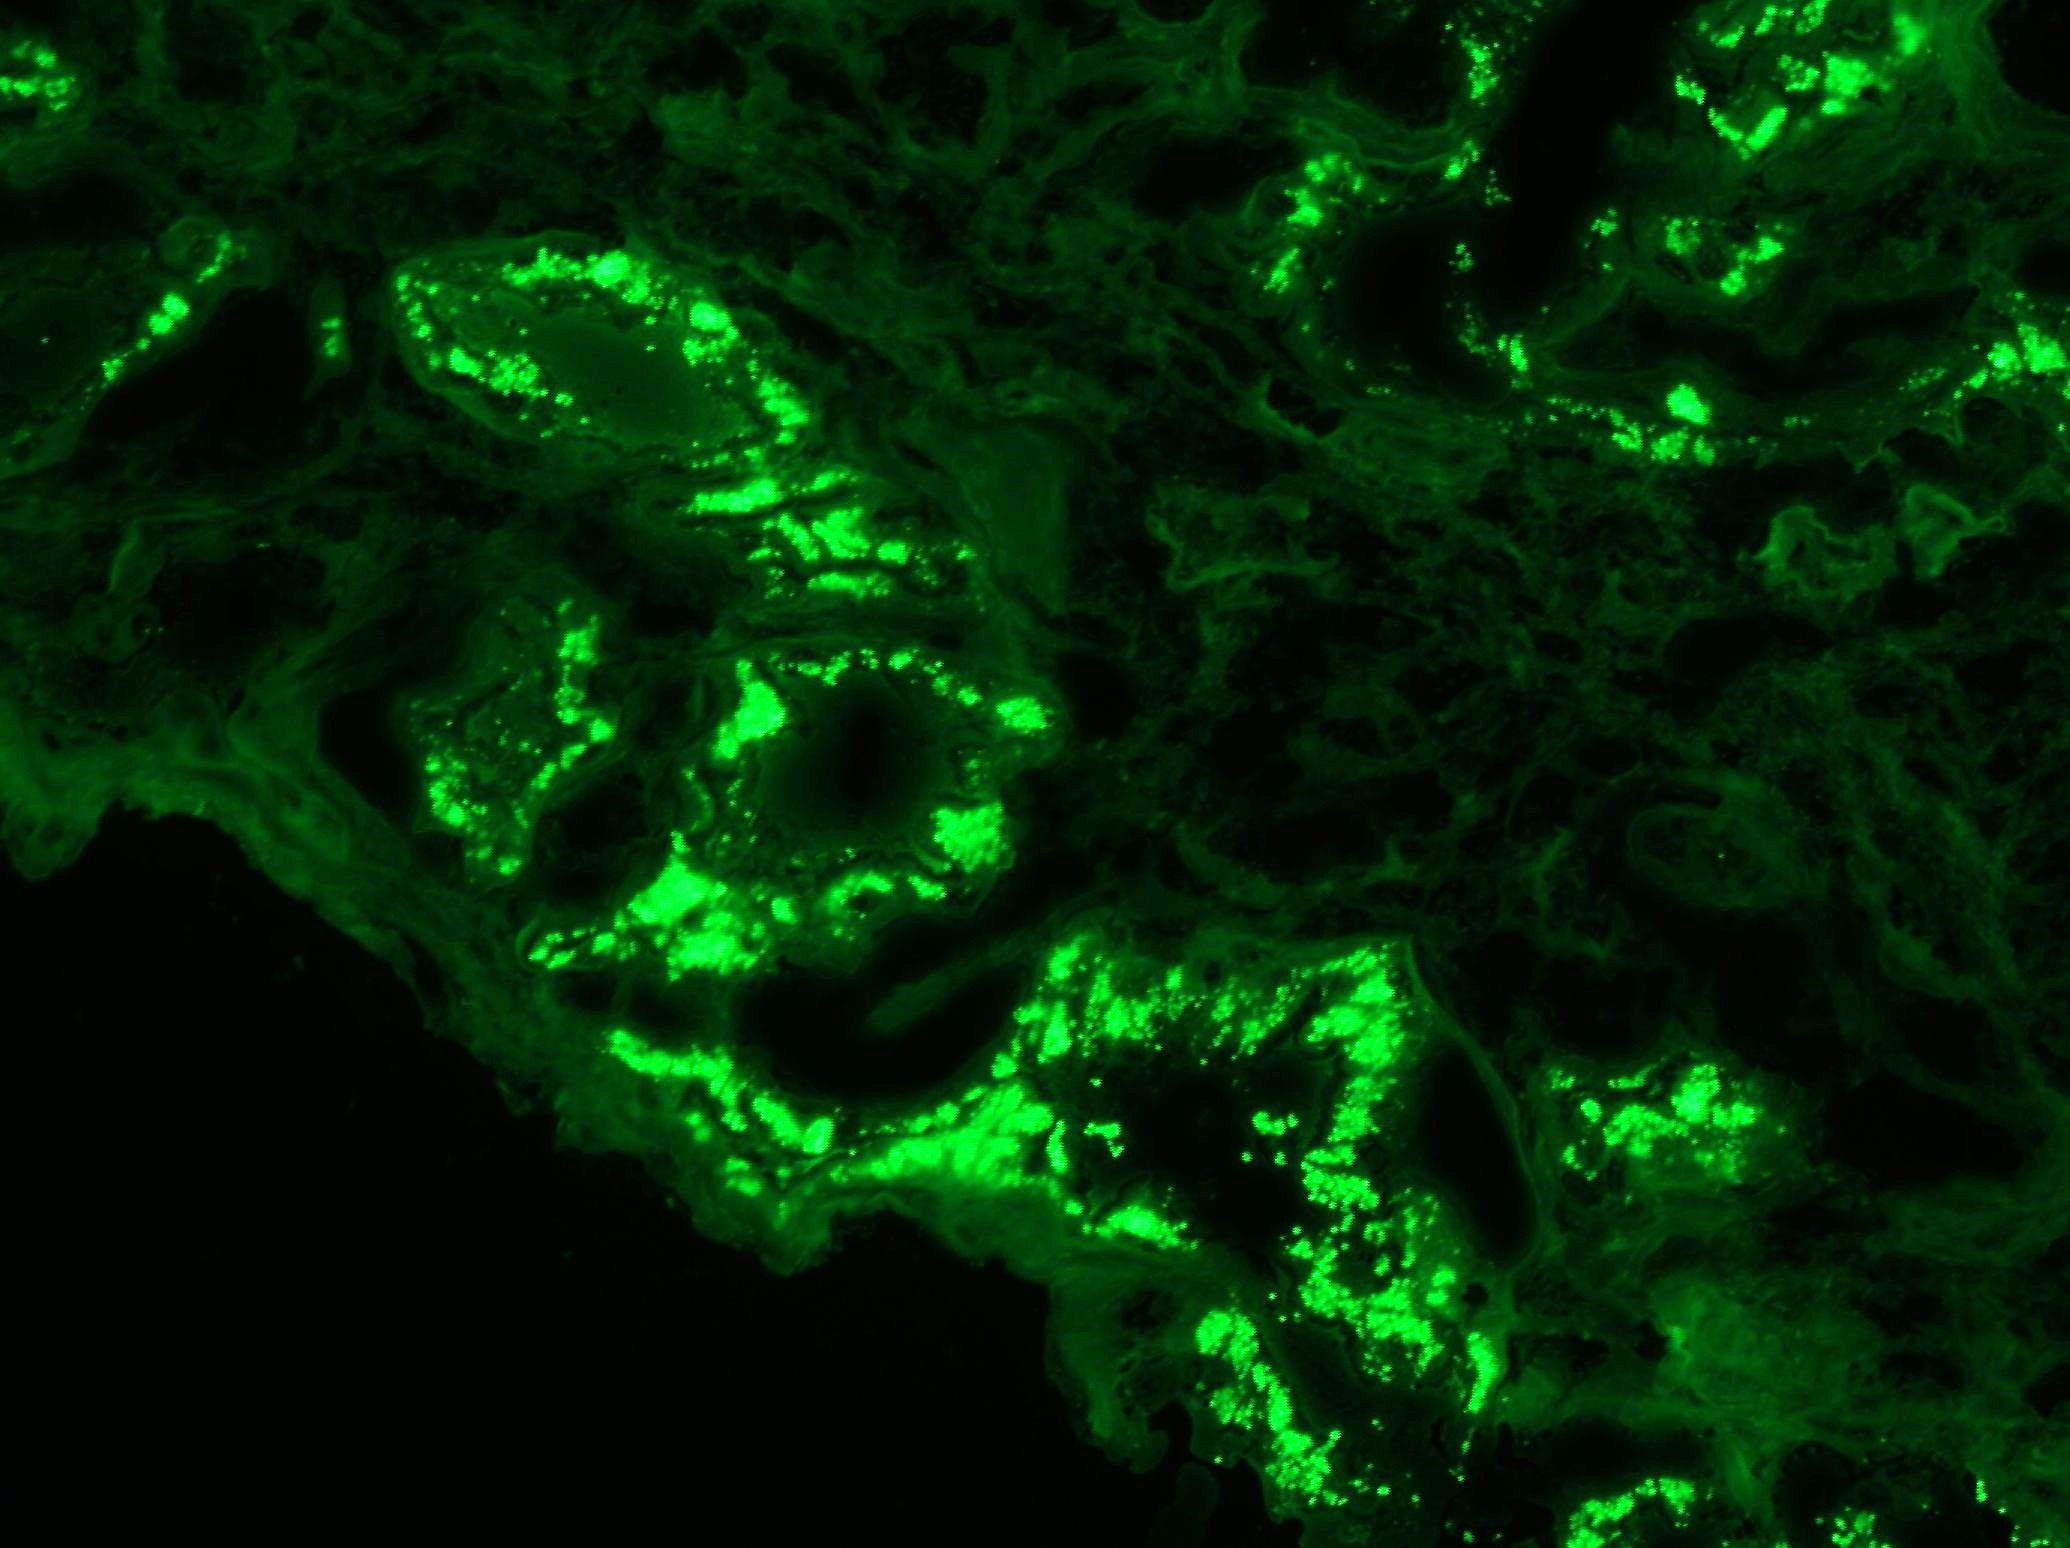

A 71-year-old man with long standing history of hypertension presented with increased serum creatinine of 3.4 mg/dL, detected during routine laboratory examination, with no associated symptoms. He was eventually seen by a nephrologist. A kidney biopsy was performed. The biopsy findings are shown in the following figures (Fig A & B: PASH stain, Fig C: Lambda- immunofluorescence stain, Fig D: Kappa- immunofluorescence stain and Fig E: Electron Microcopy of the proximal epithelial cell cytoplasm).

The diagnosis of monoclonal immunoglobulin deposition disease (MIDD) by renal biopsy often precedes other clinical evidence of dysproteinemia and is commonly the presenting disease, which leads to the discovery of multiple myeloma. The renal diseases most frequently associated with multiple myeloma/MGUS include; amyloidosis, light chain deposition disease (LCDD) and light chain cast nephropathy (LCCN). Less frequently reported is a light chain proximal tubulopathy (LCPT) characterized by kappa-restricted crystal deposits in the proximal tubular epithelial cells cytoplasm. These patients classically present with Fanconi syndrome in the setting of smoldering myeloma. Light chain proximal tubulopathy without crystal formation, on the other hand, is relatively rare and under recognized dysproteinemia related entity which by light microscopy shows nonspecific pattern of acute tubular injury with no significant casts or crystal formation (Fig A and B). However monoclonal staining of protein resorption droplets within proximal tubular epithelial cells, by immunofluorescence, provides clue to the diagnosis (Fig C and D). Electron microscopy shows increased lysosomes with irregular contours and mottled appearance within proximal tubular epithelial cells (Fig E).

Light chain proximal tubulopathy without crystal formation has several distinctions from the more commonly described LCPT with crystals. Whereas, over 90% of cases with crystals in the literature are of the kappa subtype, 90% without crystals are of lambda subtype, as seen in this case. This finding is supported by the fact that a defect in the NH2 terminal fragment of the variable domain of light chain that inhibits binding of light chain to Tamm-Horse fall proteins and promotes crystallization is commonly observed in kappa light chains. Additionally, Light chain proximal tubulopathy without crystals is more likely to be associated with multiple myeloma than LCPT with crystals and less likely to be associated with Fanconi syndrome making it a critically important diagnosis in patient with no prior history of myeloma.